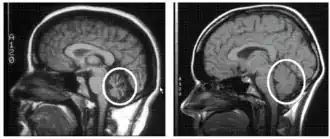

| Cerebellum (labeled bottom right) of the human brain. It is located above the brain stem, posterior to the brain. | |